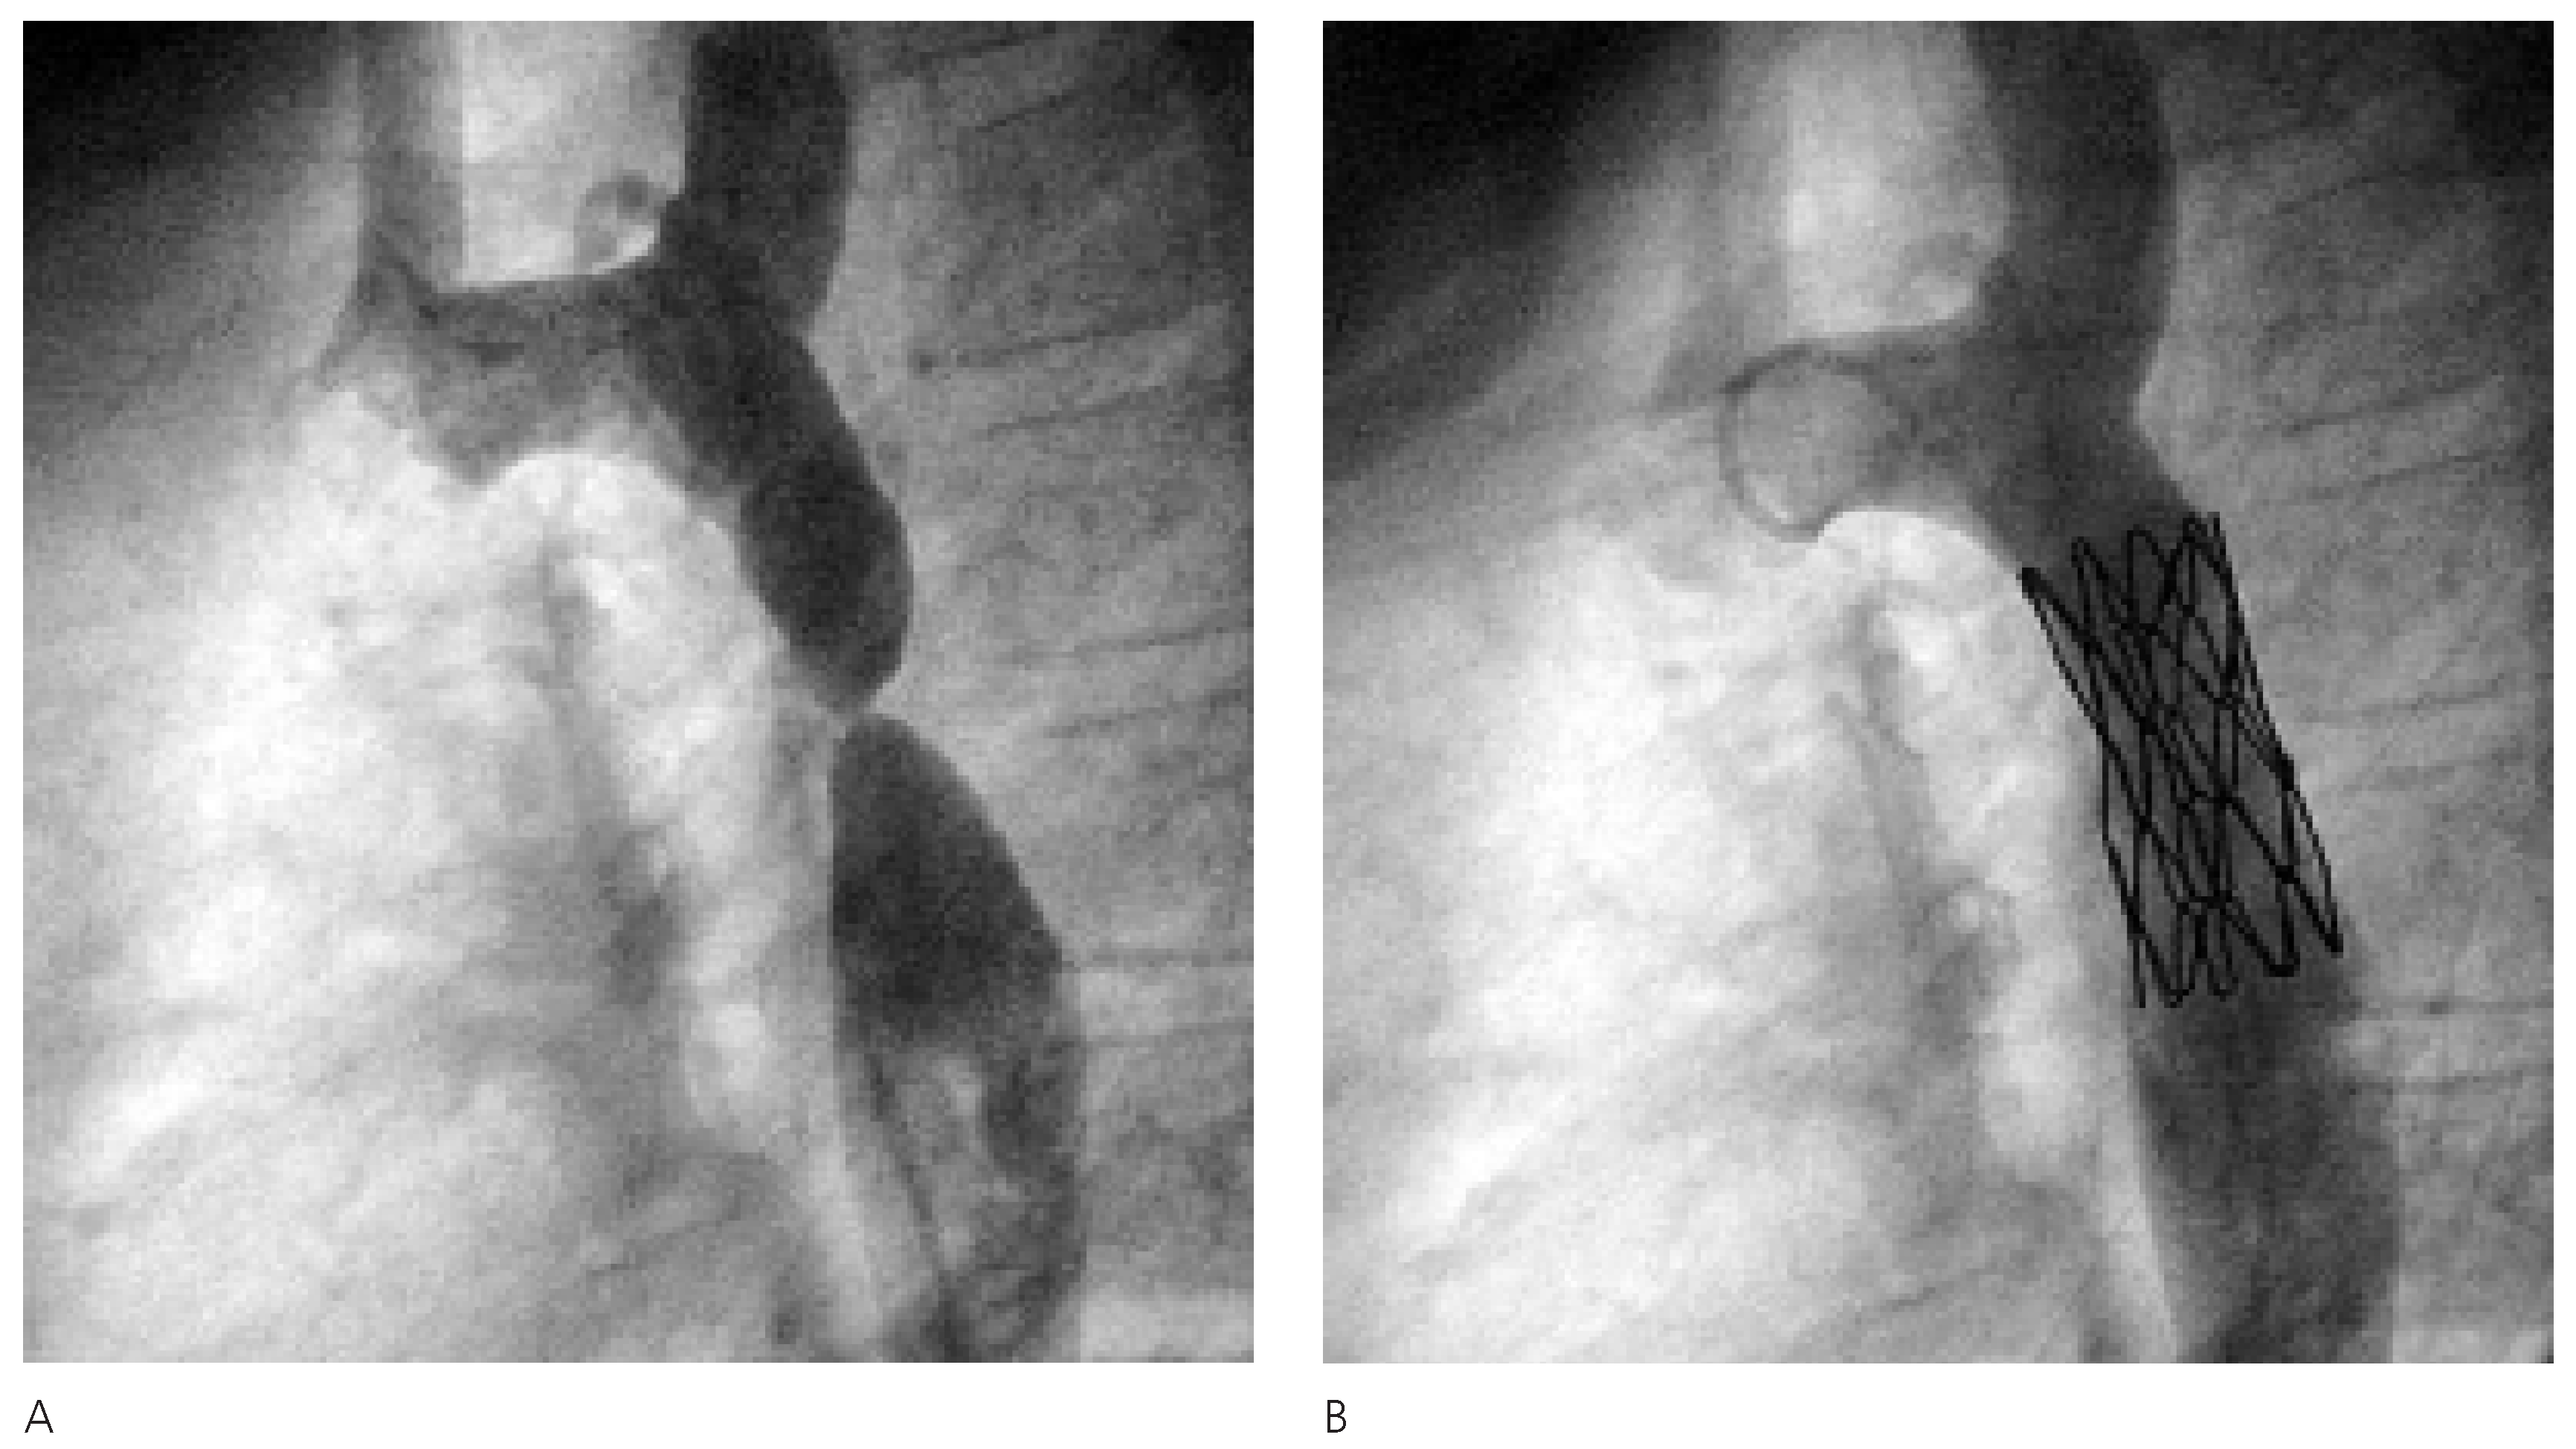

Die katheterinterventionelle Therapie gestaltete sich als komplikationslose Stent-Implantation mit Erweiterung des Aortenlumens im Bereich der AIS von knapp 1,4 mm auf 12 mm und entsprechender Reduktion des Druckgradienten von initial 40 mm Hg auf 5 mm Hg (Figure 3).

Figure 3. Angiographische Darstellung der hochgradige Stenose (A) und postinterventionelles Resultat mit korrekter Position des Stentes und vollständiger Behebung der Einengung (B).